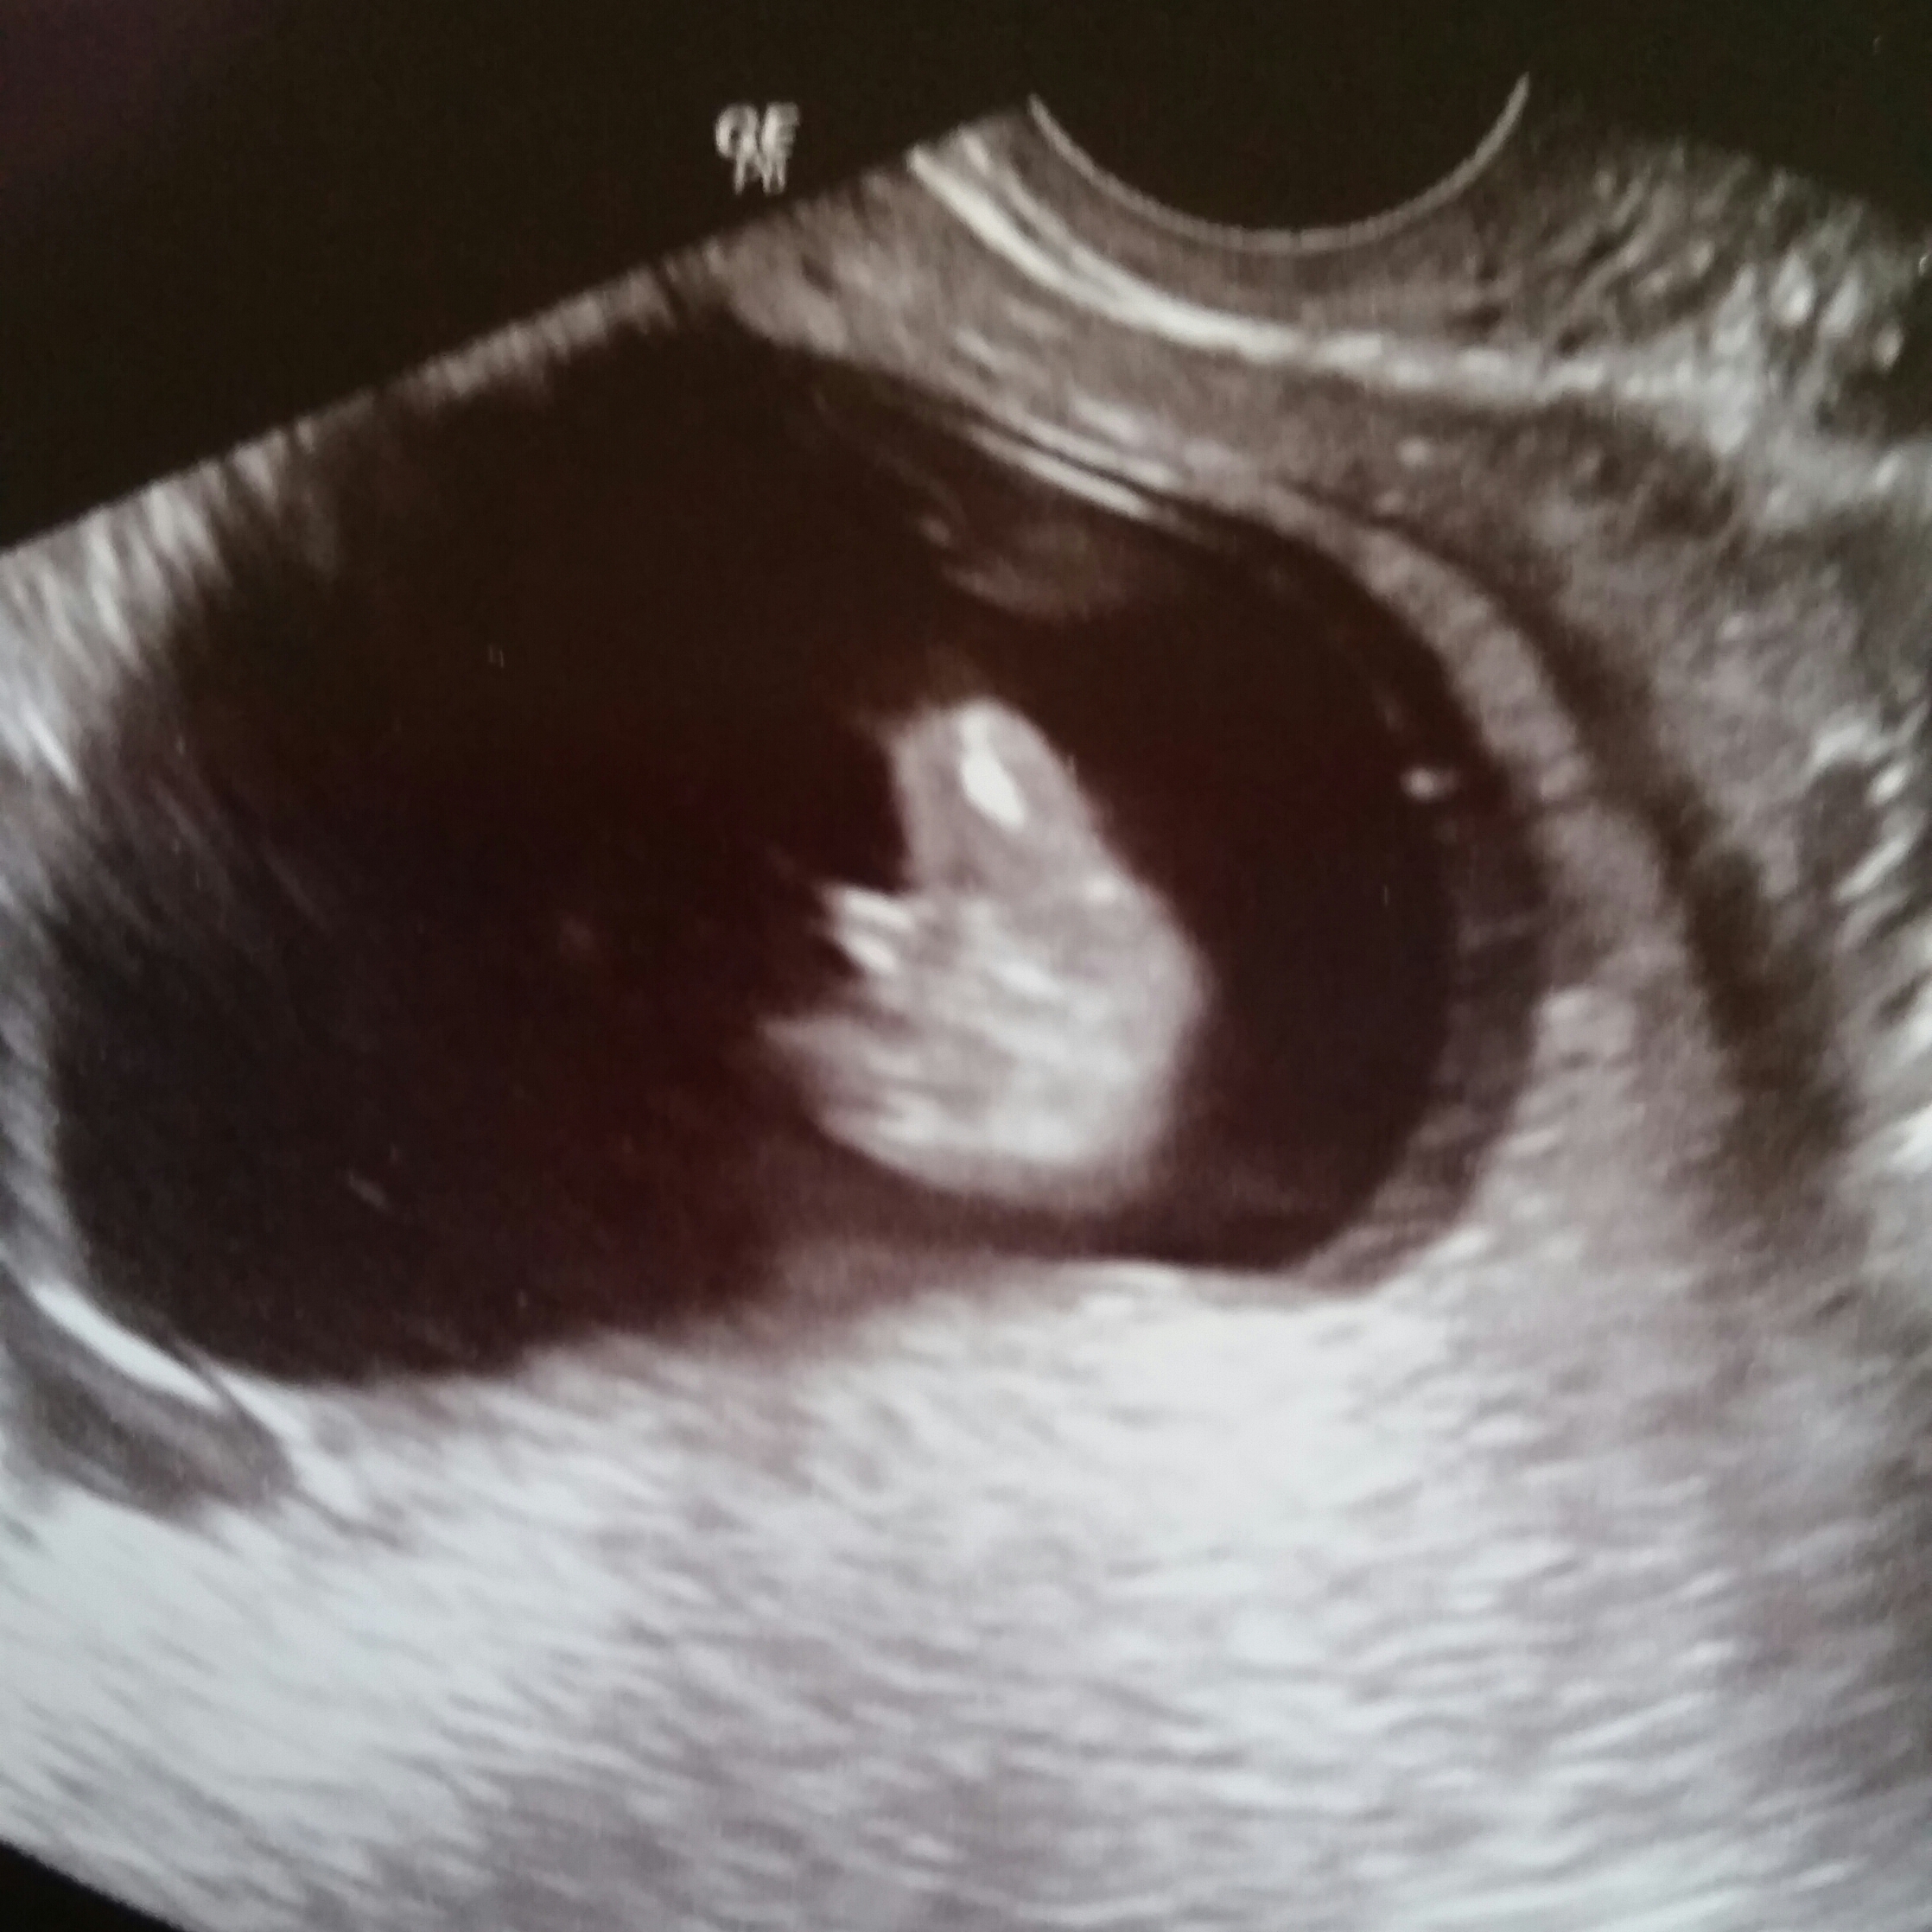

The tech said she was very familiar with the nub theory, but could not see or capture a picture of the nub. Looking over the printed photos though, I see something that may be the nub? Or maybe it is just part of the leg. Can anyone tell me if where the arrow is pointing is the nub or leg or something else??

Attachment 33198